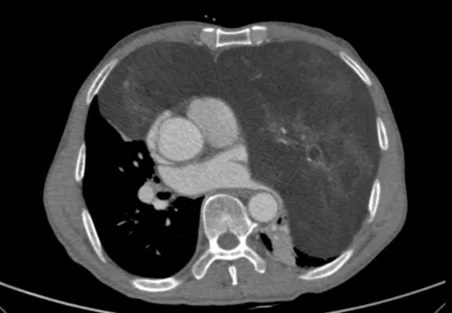

怀着忐忑的心情,家人陪同老人来到郑州大学第五附属医院胸外科就诊。完善胸部增强CT检查后,结果让经验丰富的高兴才主任也为之震惊:患者的前纵隔、左侧胸腔乃至部分右侧胸腔,被一个巨大的混杂密度团块所占据,其长径达23cm!这个巨大的瘤体几乎占满左侧胸腔,严重挤压纵隔使其向右移位,左肺因受压而萎陷。这正是导致老人长期胸闷、呼吸不畅的“罪魁祸首”。

面对这颗位置刁钻、体积巨大的肿瘤,手术切除是唯一有效的治疗手段,但风险极高。肿瘤毗邻心脏、大血管和肺组织,稍有不慎即可导致致命性大出血或重要脏器损伤。加之患者71岁高龄,心肺功能储备差,对麻醉和术后复苏提出了极大挑战。